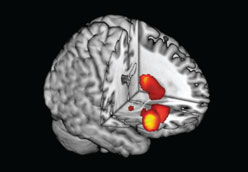

Bildquelle: Integriertes Forschungs- und Behandlungszentrum AdipositasErkrankungenDreidimensionale Abbildung eines Gehirns. Die Unterschiede zwischen Adipösen und Normalgewichtigen sieht man mit bloßem Auge nicht, dafür brauchen die Forscher ein wenig Statistik: Farbkodiert sind diejenigen Bereiche, die positiv mit dem Body-Mass-Index (BMI) korrelieren. Je höher der BMI, desto mehr graue Substanz in diesen Regionen, je heller die Farbe, desto stärker ist dieser Zusammenhang. Mögliche Ursachen für diese Unterschiede im sogenannten belohnungsabhängigen Entscheidungsverhalten fanden die Forscher in der Gehirnstruktur. „Im Magnetresonanztomographen konnten wir eindeutig erkennen, dass bei übergewichtigen Menschen diejenigen Hirnstrukturen verändert sind, die wir als Belohnungssystem bezeichnen“, beschreibt Dr. Horstmann. Genau in diesen Hirnregionen haben adipöse Menschen mehr graue Substanz als Schlanke, einer Struktur, die für die Verarbeitung von Nervensignalen verantwortlich ist. Zudem ist der Hypothalamus, eine Hirnregion, die in die hormonelle Steuerung von Hunger- und Sättigungsempfinden eingebunden ist, bei übergewichtigen Männern und Frauen stark vergrößert. Im Gegensatz dazu sind Hirnstrukturen, die an der kognitiven Verhaltenskontrolle beteiligt sind, vor allem bei übergewichtigen Frauen verkleinert. „Wichtig ist, dass diese Veränderungen nicht als Abbau von Gehirnsubstanz gewertet werden können“, betont Dr. Horstmann. Ganz im Gegenteil deuten sie auf eine andere Arbeitsweise des Gehirns hin, was vermutlich die mangelnde Impulskontrolle bewirkt.